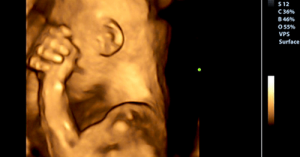

W miarę rozwoju dziecka, otrzymuje ono nieustannie sygnały od swojej matki. Jest to coś znacznie bardziej złożonego niż samo słuchanie bicia jej serca bądź słuchanie muzyki, jaką ona słucha. Dziecko słyszy znacznie więcej.

Na tym etapie otrzymuje sygnały chemiczne poprzez łożysko. Informują one dziecko o stanie psychicznym jego matki. Hormony, które produkuje kobieta, gdy pojawia się płacz ze smutku w czasie ciąży, swobodnie przechodzą przez łożysko.